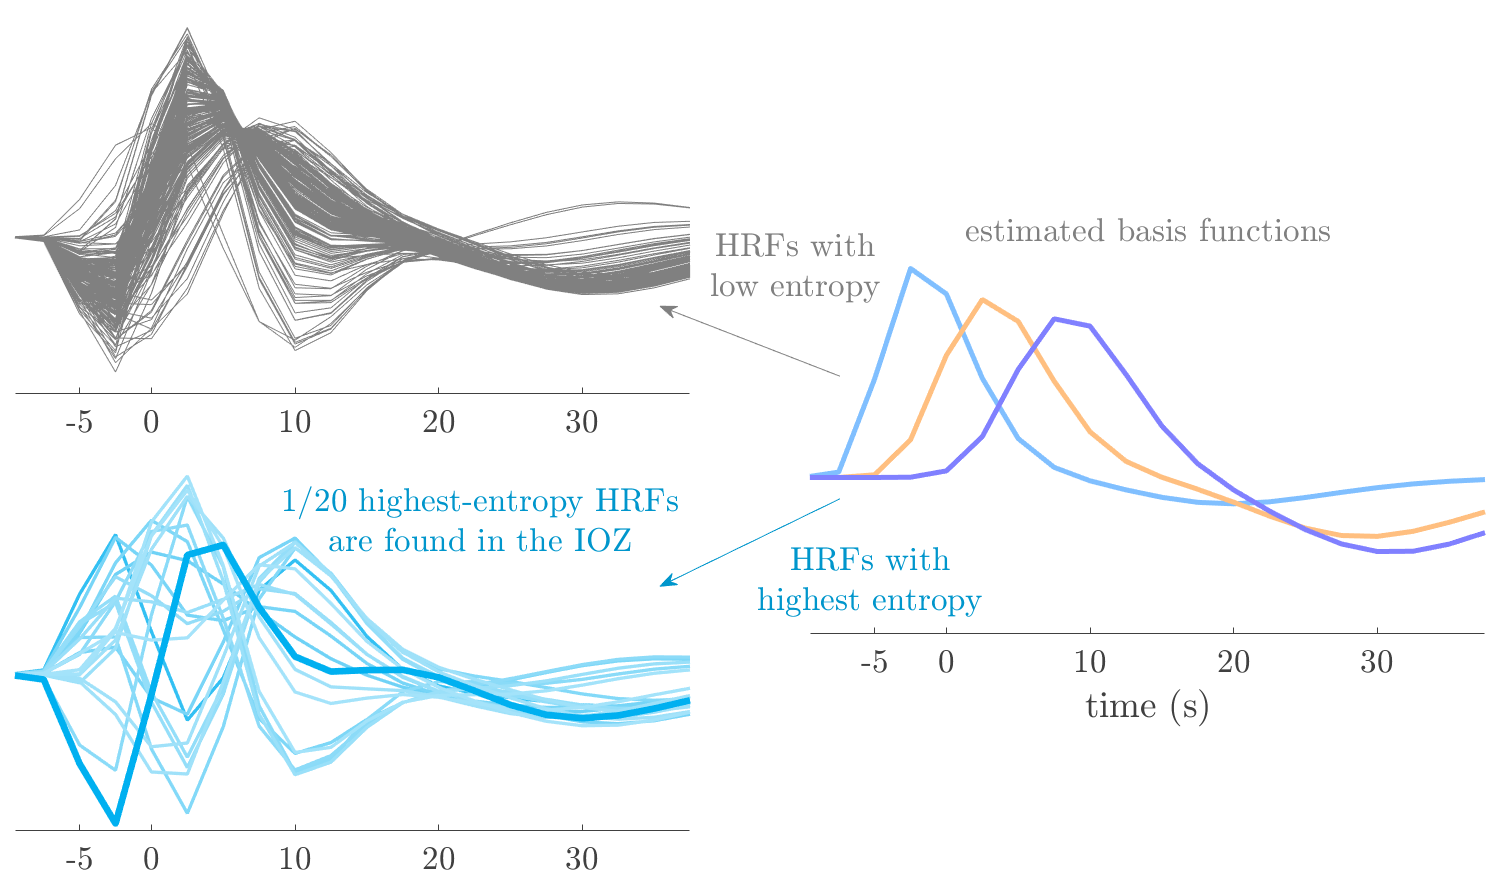

We analyze the solution with sources. Figure 1 shows the EEG signatures and HRF waveforms. One of the sources is highly correlated to the MWF reference (in grey), which was already known from Table B.3. This IED-related source had a typical low-frequency spectrum, which is expected for the typical spike-and-wave interictal discharges. The topography is relatively diffuse, although the highest amplitudes are mostly in the left hemisphere. This is in accordance with the lateralization of ictal onset zone (left temporal lobe, cfr. Table 1). There are some noteworthy observations to be made about some of the other components. The fourth has an unusually sharp spectrum, is mainly localized on two nonadjacent center electrodes, and is sustained for a single period of many seconds Hence, this component likely captured an artifact (of yet unknown origin), although we spotted no large-amplitude changes in the EEG itself. Similarly, the third source is only present at one frontal electrode, and exists in a frequency range above 20 Hz. It might represent a muscle artifact, e.g., due to frowning or twitching of some muscles in the forehead. The HRFs of all ROIs are shown in Figure 1(b). Two of the basis functions seem to have converged to a very similar waveform, which is an unfortunate possibility if two initial HRFs are too close to the same local optimum in their respective parameters. This reduces the expressive power of the basis set, which is clearly visible, since many ROIs have a nearly identical HRF. One of the twenty ROIs with the highest-entropy HRF overlapped the IOZ, although clearly this HRF (bold line) is not among the most dissimilar waveforms for this patient. This is also visible in Figure 2: both the HRF entropy and extremity maps show a small overlap with the delineated IOZ. Despite the good correspondence in the EEG domain, no significant (de)activation of the IED-component is found inside the IOZ.

We analyze the solution with sources, and show the results in Figure 3 and 4. As for patient 1, we found a source which is strongly correlated to the MWF envelope, and which had a mostly low-frequency behavior characteristic for spikes. The topography is mostly uninformative, and does not clearly correspond to the patient’s clinical data. The third source is mostly present at both sides of the head, is very sparsely active in time, and has a high-frequency content: this is most likely an artifact due to the neck muscles. Again, there is one of the highest-entropy HRFs which belongs to a ROI in the IOZ. Now, the waveform is clearly resolved from the other HRFs, through the strong initial dip (before 0 seconds). Such a dip is sometimes observed in HRFs, but its underlying physiological mechanism is not yet fully understood. It is possible that this dip reflects altered vascular autoregulation near the IOZ (cfr. the explanation in the Section 1 of the main text), or a rapid depletion in oxygen due to IED generation (before the IED becomes visible on the EEG). Figure 4 furthermore shows that the IED-related component is significantly active in parts of the IOZ, and deactive in others. As mentioned earlier, this deactivation may or may not be due to errors in sign correction. Interestingly, the ROI with the high alteration in neurovascular coupling is distinct from both the activated and deactivated ROIs.

We analyzed the solution with sources, and show the results in Figure 5 and 6. There is one source which is mostly correlated to the reference (but not extremely, see also Table B.3). This source had a right-temporal focus, conform the diagnosis in Table 1. The second source illustrates the phenomenon of an erroneous sign exchange between the spatial and spectral profiles. Also one of the HRFs has a negative polarity, which is a failure of the sign correction procedure (in this case, because there is exceptionally no positive overshoot). However, the HRF variability metrics are still interpretable, and indeed two ROIs among the ones with the highest-entropy HRFs overlap with the IOZ. The IED component is significantly active in a tiny portion of the IOZ (cfr. Figure 6). The second source is significantly active in symmetrical parts of the parietal lobe. Given its ongoing fluctuation over time, we hypothesize that this source captures a resting state network (RSN).

We analyze the solution with sources, and show the results in Figure 7 and 8. There is a clear IED-related component, with a very high correlation to the MWF reference, a typical spectrum, and an anterior-temporal focus, which corresponds very well to the patient’s diagnosis (cfr. Table 1). The fifth source seems present at only one channel, and has spectral harmonic at Hz and Hz. One of these peaks is reminiscent of the fourth component in patient 1. As Figure 8 shows, the HRF entropy and extremity prove to be strong biomarkers for the IOZ in this case, and also the significant IED activation and deactivation allow correct localization. In Figure 7, it is clear that some HRFs may still have the wrong sign, which means that the interpretation of ‘active’ and ‘deactivated’ is flipped in those ROIs. Hence, regions of significant deactivation are in fact significantly activated. The fourth source had a significant overlap with the auditory RSN, and its spectrum reveals activity in the band.

We analyze the solution with sources, and show the results in Figure 9 and 10. One source is strongly correlated to the MWF, while the other source is likely an artifact, given its very sparse temporal profile. Both sources coincide at one high-amplitude peak, by which we infer that this is probably an artifactual period in the signal. Indeed, when inspecting the original EEG signals, we found high-frequency muscle artifacts at these times. This source also had no significant activation in its spatial map, which corroborates its non-neuronal origin. The IED-related source had a broader spectrum than most other cases, and an uninformative topography. None of the ROIs with high-entropy HRFs is located in the IOZ. The pseudo t-map provides correct localization of the IOZ, however.

We analyze the solution with sources, and show the results in Figure 11 and 12. We found a clear IED-related component, with a characteristic spectrum and a topography which is backed up by the patient’s diagnosis (left anterior-temporal IOZ). The fourth source has a very similar topography and spectrum to the fifth source in patient 5. One HRF inside the IOZ had a high-entropy, and is distinguishable from the others by its very sluggish waveform, i.e., it is smeared out in time, with no sharp over- or undershoot. Also the pseudo t-map provided an accurate localization of the IOZ. Notably, in this patient, the extremity metric misses the deviating HRF in the IOZ (while the entropy metric picks it up). The second source overlapped with the frontal part of the default mode network (DMN), and is active in the and low bands.

We analyze the solution with sources, and show the results in Figure 13 and 14. We found two components which had correlated time courses. At the time of the peaks, we found higher-amplitude events in the EEG with dubious origin, hence they may or may not be artifacts. One of both components is more strongly correlated to the MWF, and its activation is concordant with the IOZ. The second component shows high overlap with the sensorimotor network. For this patient, none of the IOZ’s ROIs had extreme values of either HRF metric.

We analyze the solution with sources, and show the results in Figure 15 and 16. In this patient, there is only a moderate correlation of a component with the MWF reference time course. This component’s topography (left occipital) agrees with the clinical description, however. The HRF extremity (and not the entropy) is high in a small part of the IOZ. Both the significant IED activation and deactivation allow correct localization as well. The second source seemingly captured high-frequency oscillatory activity in the sensorimotor network, similar to the previous patient.

We analyze the solution with sources, and show the results in Figure 17 and 18. The IED-related source had a high correlation with the MWF reference, but an odd bimodal spectrum. Its EEG topography is very consistent with the clinical description. Both HRF extremity and entropy are useful biomarkers for the IOZ. The IED activation and deactivation maps each had a very small overlap with the IOZ. The second source is temporally sparse and captures high-frequency EEG variations, which we identified as muscle artifacts.

We analyze the solution with sources, and show the results in Figure 19 and 20. Again we observe an IED-related source and a seemingly artifactual source with a spectral peak near 34 Hz. Many of the high-entropy HRFs are highly noncausal, and are associated to ROIs inside the IOZ. Hence, with both HRF metrics, the highest-scoring ROIs provides good localization of the HRF. While there are no significantly active ROIs in the IOZ, there are several significantly deactivated ROIs, which may indicate that the sign standardization was not done flawlessly (cfr. also some of the negative-peaking HRFs for patient 10). Surprisingly, the second source had one significantly active ROI, which overlaps with the IOZ, but which did not match its EEG topography. Hence, the nature of this source remains ambiguous.